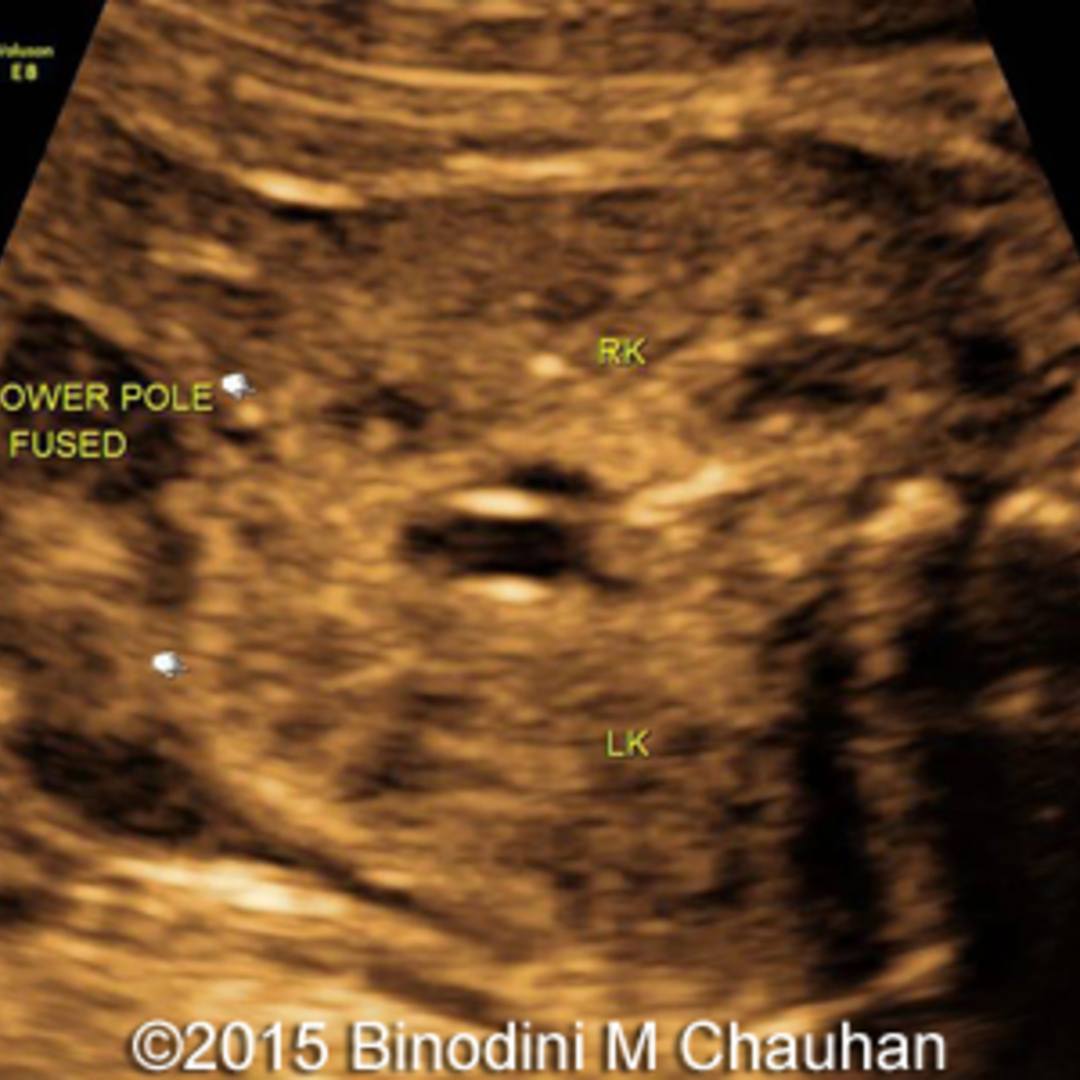

Target ultrasound Horseshoe kidneys & other abnormalities in fetus Horseshoe Kidney In Fetus horseshoe kidney is when the 2 kidneys join (fuse) together at the bottom. Usually, two individual kidneys form in. Horseshoe kidney is found in 30% of cases of turner syndrome and in 20% of trisomy 18. horseshoe kidney occurs in about 1 in 500 children. It occurs during fetal development as the kidneys move into their normal position. Horseshoe Kidney In Fetus.

📃 Horseshoe kidney with unilateral multicystic dysplasia Horseshoe Kidney In Fetus A fetal pelvic kidney is a condition that results when the kidneys fail to ascend to their normal position above. horseshoe kidney is when the 2 kidneys join (fuse) together at the bottom. Usually, two individual kidneys form in. horseshoe kidney occurs during fetal development, as the kidneys move into their normal position in the flank area (area.. Horseshoe Kidney In Fetus.